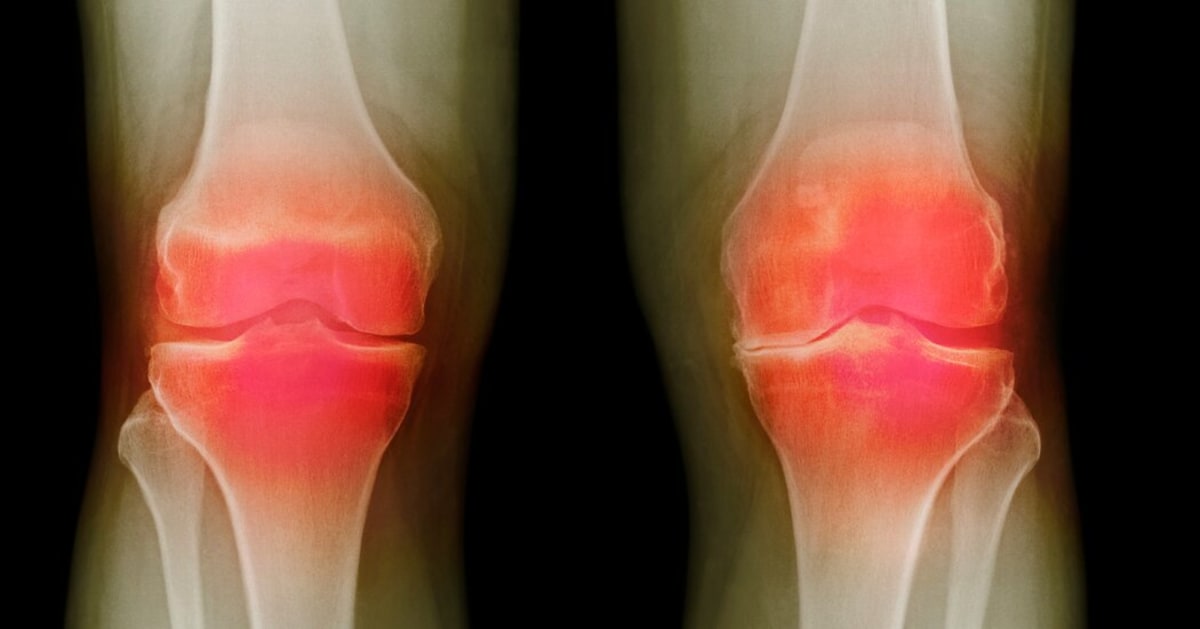

Scientists may have finally cracked the code on curing osteoarthritis, a painful joint condition that affects 32 million Americans and has no real treatment beyond managing symptoms.

The Advanced Research Projects Agency for Health (ARPA-H) just announced that three research teams have developed treatments that regrow bone and cartilage in damaged knees. The most ambitious project might even regrow an entire knee joint from scratch.